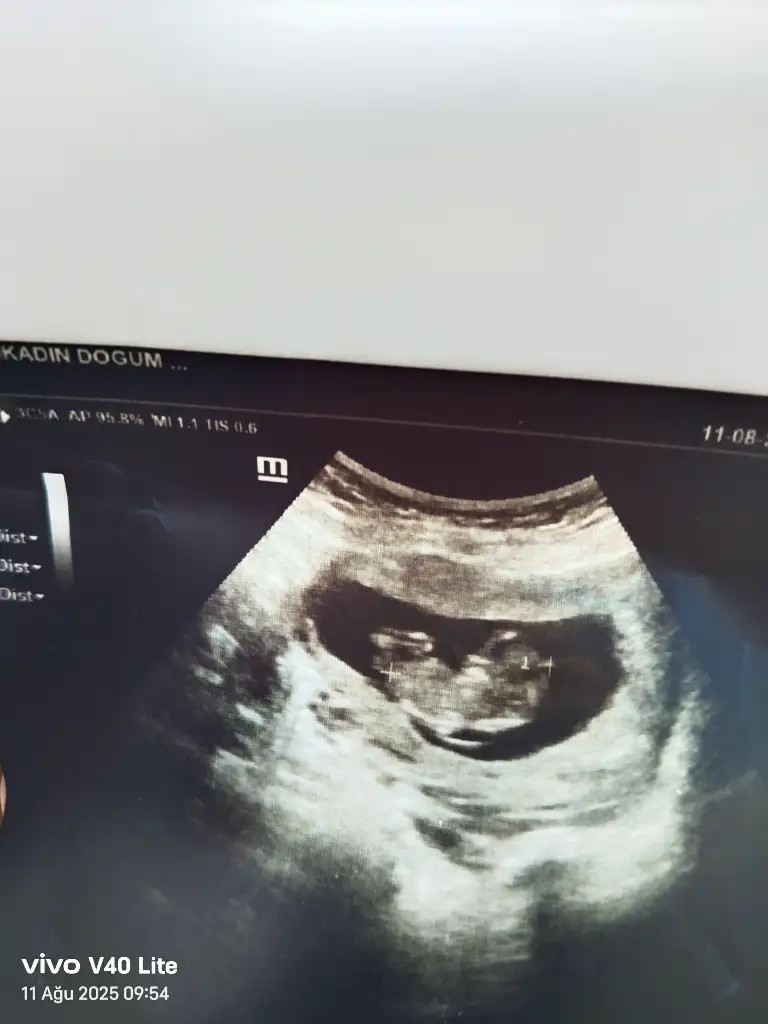

Merhaba benimde yorumlarmisiniz rica etsem 11+1Bariz erkek görüyorum, sağlıcakla gelsin inşallah![]()

Sizce benim nedir 11+1Erkek bence

Kesesini erkeğe benzettim sağlıkla gelsinSizce benim nedir 11+1

TeşekkürlerKesesini erkeğe benzettim sağlıkla gelsin![]()